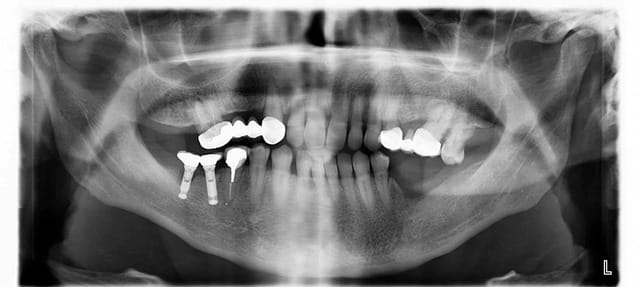

Est ce quelqu'un reconnait ces implants ?

Posés il y a 20 en Espagne. La secrétaire a retrouvé la fiche du patient ou il est écrit "Biopech, 3,8x8". Rien de plus...

D'après le peu que je trouve sur internet, et si je mesure sur ma radio on est plus sur un 3,3.

http://osseosource.com/dental-implants/product_info.php?products_id=1116

sterioss en 3.8mm

On m'a dit chez Dentsply que ce ne sont pas des IMZ a priori.

Ils m'ont orienté vers des calcitek (repris par Zimmer) mais ce n'est pas ça non plus !

J'ai réussi a récupérer ça chez le poseur...

Des (nouvelles)idées ?

je te répète: c'est des sterioss en 3.8mm

pour les pièces, c'est le groupe Danaher qui assure (normalement) le suivi (et donc Implant Direct)...s'il reste encore des pièces...

C'est justement implant direct qui m'a orienté sur de l'IMZ